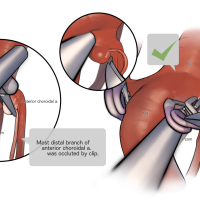

術後イラストシリーズ

OPExPARKコンテンツ・脳神経外科速報寄稿シリーズ